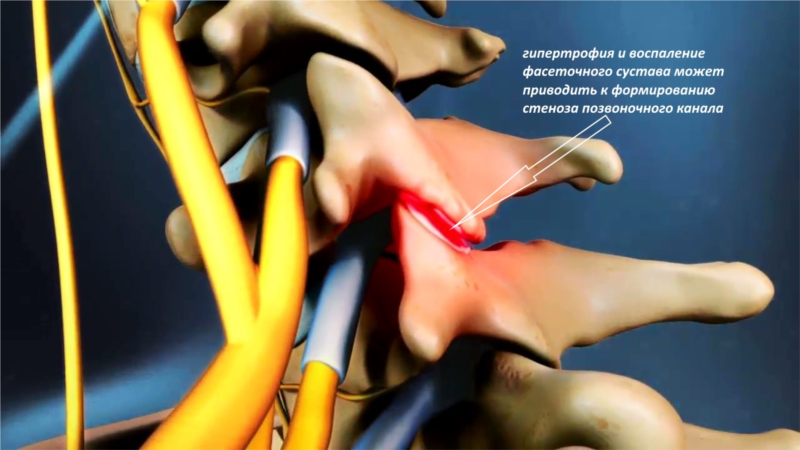

Остеоартрит фасеточных суставов: медицинские снимки и схемы